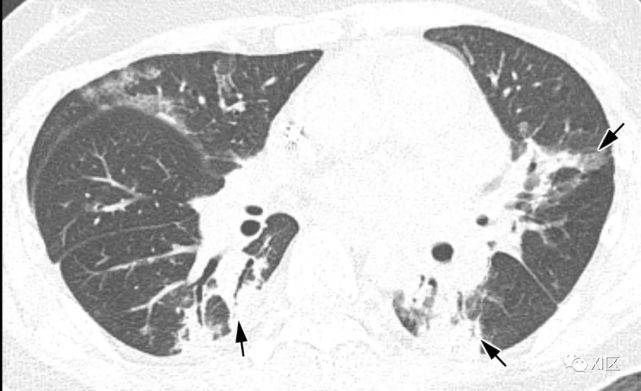

图14 一位22岁女性感染前1个月因急性淋巴细胞白血病接受单倍体相合骨髓移植治疗,有发热,诊断为 HPIV病毒性肺炎。

在主支气管水平(上)和叶间区水平(中上)的初始轴位胸部CT图像显示沿支气管血管束和轻度支气管壁增厚(箭头)的多灶性不明确结节性GGO病变(箭)。中性粒细胞减少持续存在。(中下,下)随访10天后获得的轴位胸部CT图像显示病变的范围和强度增加,并沿支气管血管束增加不规则的实变结节(箭)。尽管进行了重症监护,该患者仍然死亡。

Koo H J , Lim S , Choe J , et al. Radiographic and CT Features of Viral Pneumonia[J]. Radiographics, 2018, 38(3):719-739.